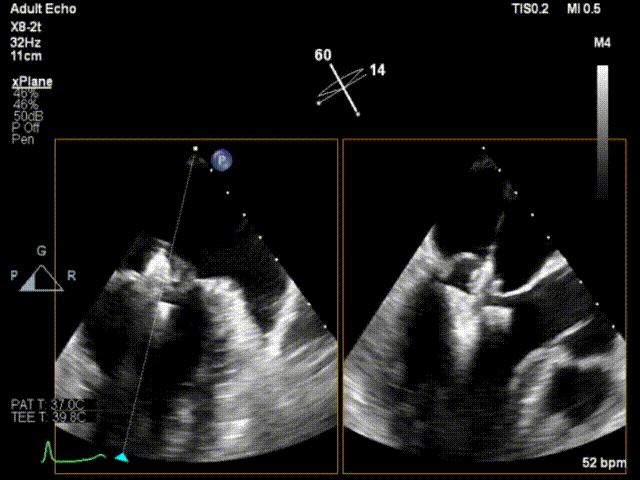

手术运用DSA与三维经食道超声心动图监测,通过患者股静脉穿刺房间隔途径建立夹合器输送轨道,将夹合器送进左心房,借助夹合器输送系统通过病变的二尖瓣部位,在心脏不停跳的状态下快速完成二尖瓣脱垂瓣叶的破获和夹合,夹合位置满意,超声提示反流降至1+,遂释放夹合器,反流最终程度为1+,结束手术,手术过程耗时一小时左右。

术中瓣叶捕获